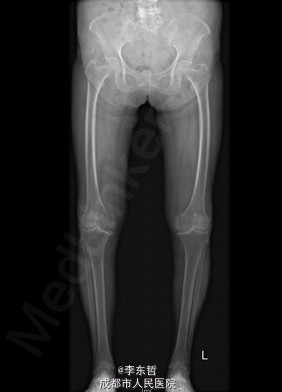

患者女,74岁,因“双膝疼痛20年,加重伴行走困难8年”入院。患者诉20年前开始出现双膝关节疼痛,负重行走、下楼时疼痛加重,休息后可缓解,尚可下蹲。自行购买止痛药口服,关节腔内注射玻璃酸钠、理疗等处理,疼痛时有缓解。但症状反复发作。8年前疼痛加重且行走困难,扶拐行走仅能坚持约10余米,上下楼梯艰难,下蹲不能,以左侧为重。遂来院就诊。

查体:跛行步态,双膝关节屈曲内翻畸形,双膝内侧间隙压痛,双膝髌股关节间隙压痛,左膝伸-20°,屈110°内翻10°。右膝伸-20°,屈110°内翻10°,双膝屈伸活动时髌骨下摩擦感(+)。 辅助检查:X片示双侧髌股关节内侧间室变窄,关节边缘骨赘增生,软骨下骨硬化。

入院诊断:1、左膝骨关节炎伴屈曲内翻畸形; 2、右膝骨关节炎伴屈曲内翻畸形; 诊疗计划:1、向患者及家属交待病情及注意事项。2、向上级医生汇报患者病情。3、完善相关术前检查;4、择期手术。